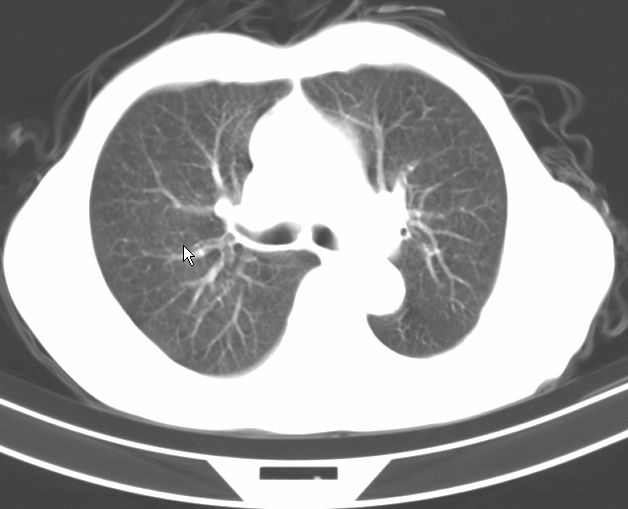

标题: CT17095:胸部病变请大家看看是什么性质的

请大家看看是什么性质的。炎性病变首先考虑哪一种炎症。

支持右肺上叶前段\\下叶内基底段感染,建议抗炎治疗后复查,除外结核.

支持右肺上叶前段\\下叶上段感染,建议抗炎治疗后复查,除外结核.

支持右肺上叶前段、下叶内基底段感染,建议抗炎治疗后复查,除外结核.

右肺上叶前段及下叶内基底段感染性病变;建议抗炎治疗后复查。

楼主说是炎症,凭啥?典型的周围型肺癌(腺癌可能性大),肝内可能已有转移,强化看看吧。